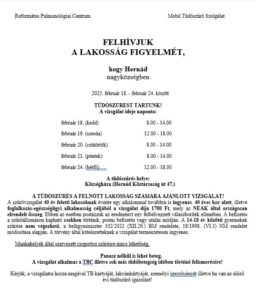

BypamaPolgármester asszony az elmúlt héten eljuttatta a helyi egészségügyi szolgáltatókhoz azokat az eszközöket, amelyeket a Magyar Falu Program 2020 „Orvosi eszköz” alprogramjának támogatásával vásárolt az önkormányzat. A pályázatot idén március 25. és április 24. között lehetett benyújtani. Az önkormányzatnak öt egészségügyi szolgáltatója van (két háziorvos, gyermekorvos, fogorvos és a védőnők). Mindannyian kértek új eszközöket, amelyeket…